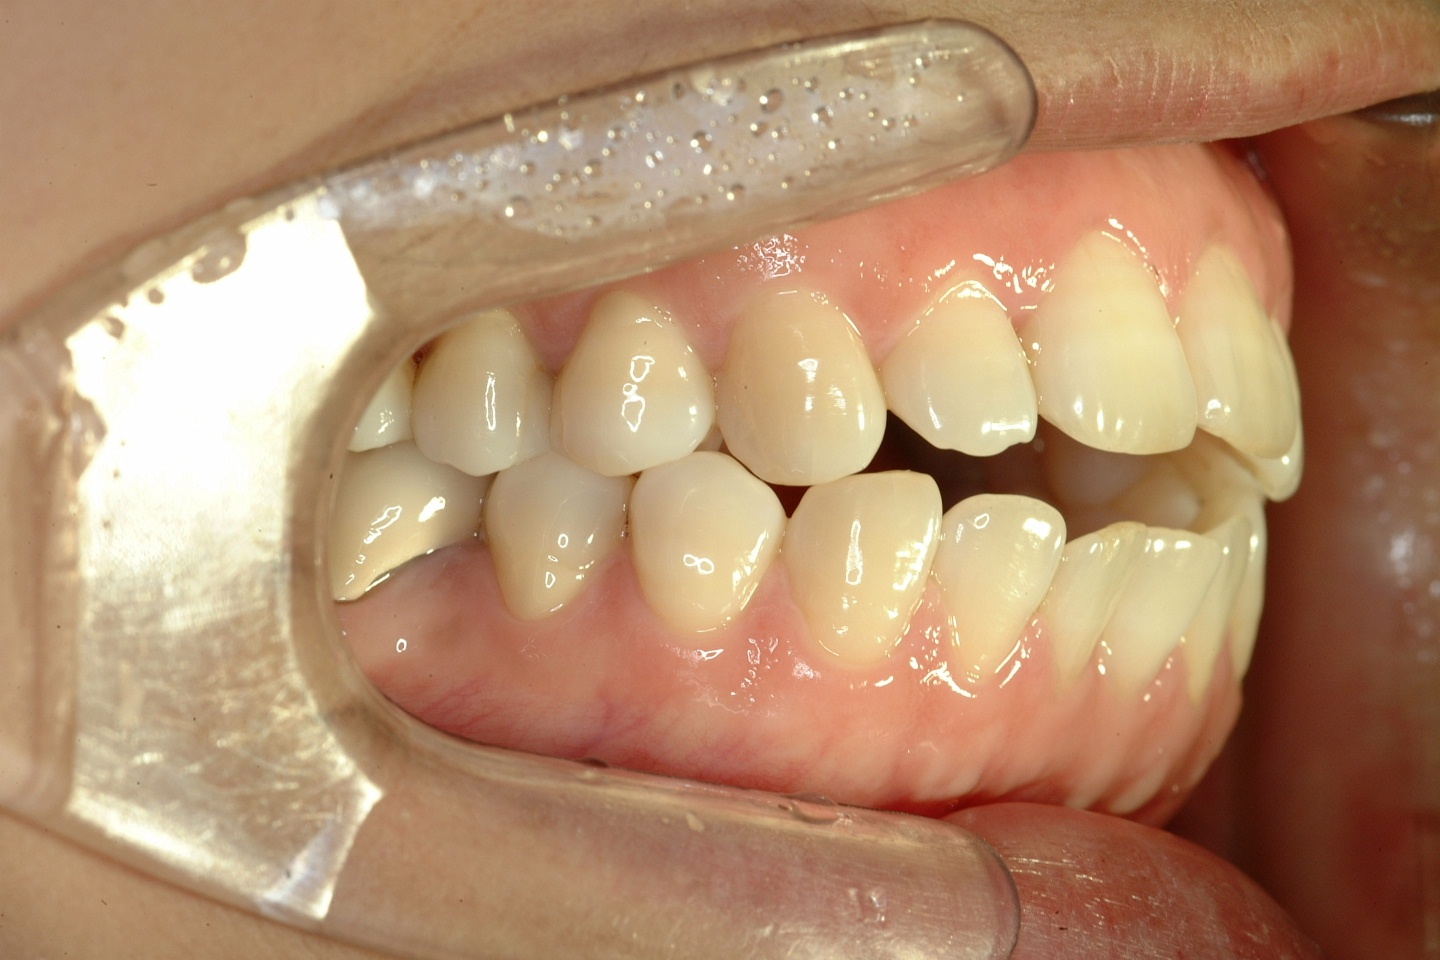

치료 후 사진입니다.